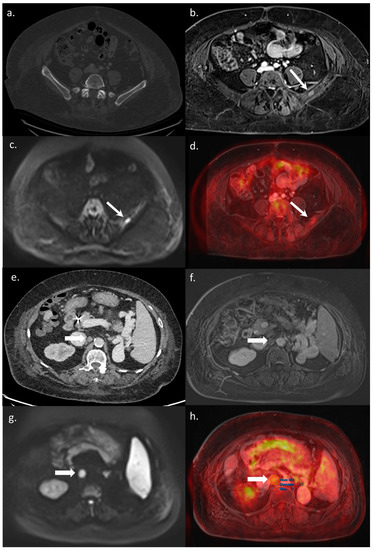

Figure 3. A 65-year-old BCLC C patient referred for a WB-PET/MRI before liver transplantation. On CT-CAP, no bone lesion was visible (a). The WB-PET/MRI revealed an infracentimetric bone lesion with enhancement after Gadolinium–chelate injection (b), together with hyperintensity on DWI (c), and focal hypermetabolism on 18F-FDG-PET (d) leading to the diagnosis of bone metastasis. Moreover, on CT-CAP, a retroperitoneal nonspecific lymph node was observed (e), visible on morphologic MRI sequence (f). Both diffusion restriction (g) and 18F-FDG hypermetabolism (h) were observed leading to the diagnosis of lymph node involvement. The patient was excluded from the liver transplantation list, with a rapidly progressing disease leading to patient death within three months.

All 14 metastatic sites were correctly identified on the WB-PET/MRI, although only 7 of 16 individual pulmonary metastases (44%) were seen (Figure 2). On the CT-CAP/liver MRI dataset, six metastatic sites were correctly identified (6/14; 43%), resulting in a significantly lower sensitivity (43% vs. 100%, p = 0.002). Notably, all 10 individual bone metastases were missed on the CT-CAP/liver MRI (Figure 3), as well as two mediastinal lymph nodes (Figure 4) and one retroperitoneal lymph node involvement (Figure 3).

The WB-PET/MRI lead to changes in therapeutic management in 10 of 104 patients (9.6%). Metastatic lesions were identified by the WB-PET/MRI in two BCLC stage C patients referred before liver transplantation (Figure 3) and in five BCLC stage C patients referred before TARE (Figure 2 and Figure 4).